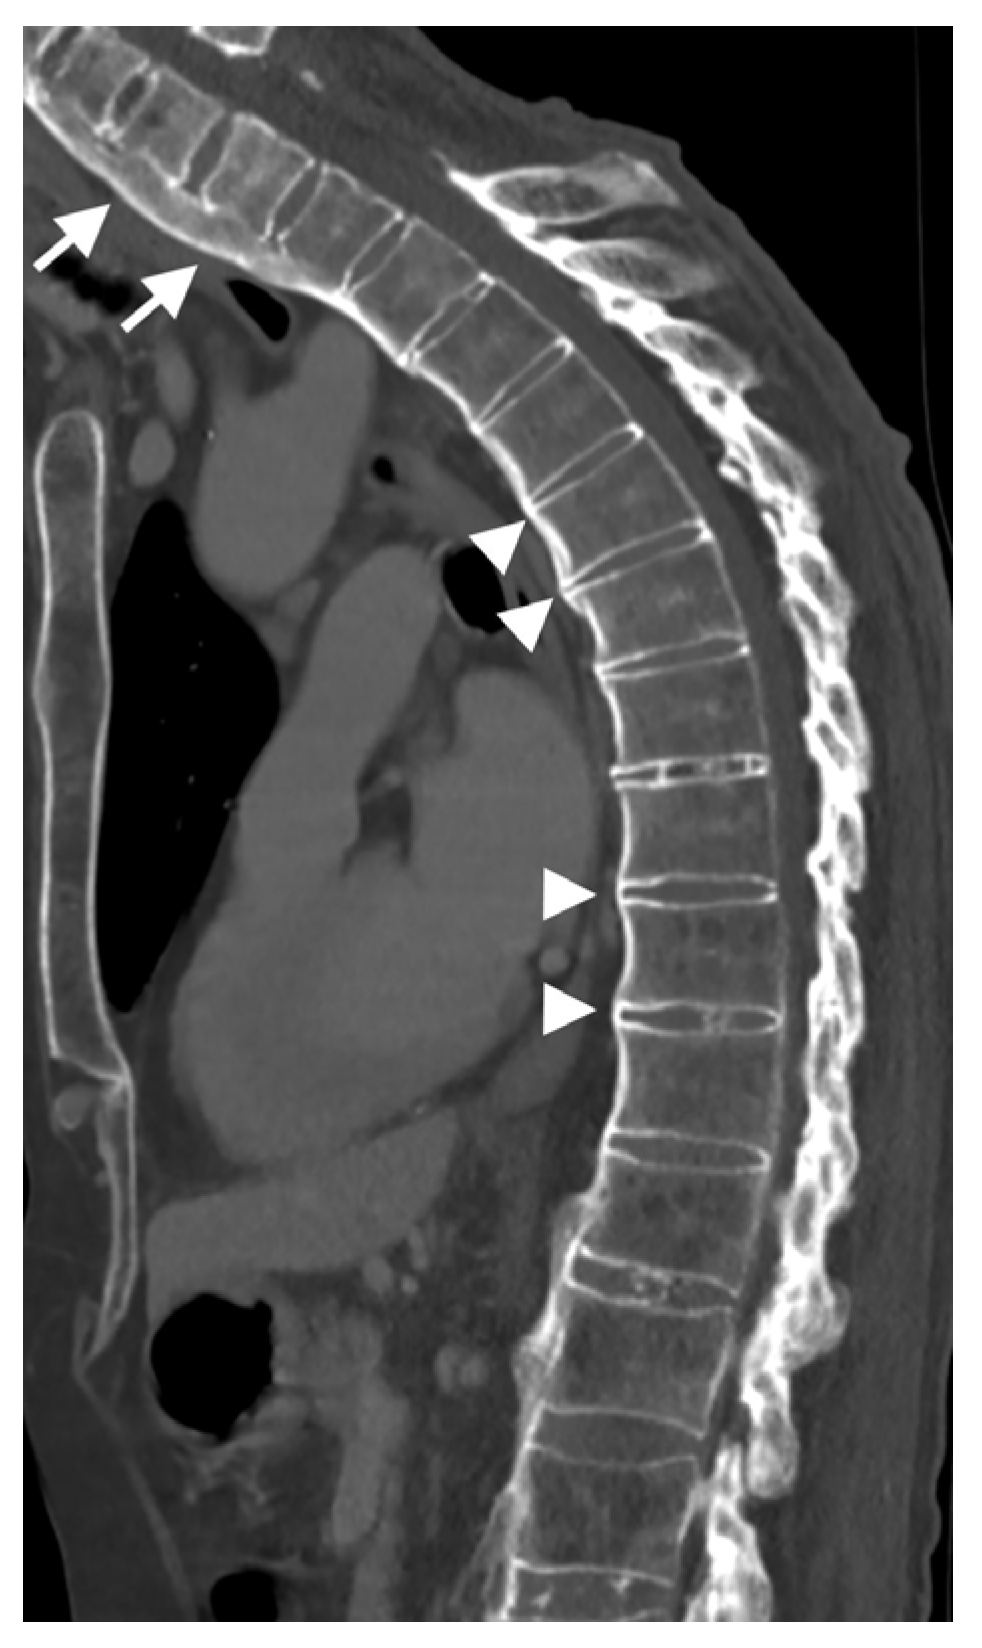

An ankylosed spine, such as that observed in DISH, is rigid and, as a result, is susceptible to injury, even from low-energy trauma. DISH is associated with a prevalence of thoracolumbar vertebral fractures of 4–18%, of which multilevel fractures are reported in about 8% [56,57]. These fractures are frequently extension-type fractures and are associated with a greater instability risk for spinal cord injury of up to 58% and a higher rate of complications (Figure 6) [58,59,60]. Fractures in DISH pass through the vertebral body, which is the most exposed and weakest point in the ankylosed spine [61]. Detection of vertebral fractures on radiographs of the spine of DISH subjects is challenging; thus, it has been suggested that whole-spine CT be performed in emergency response units in order to prevent negative consequences in DISH subjects, even after minor trauma [9,62].

Figure 6.

Sagittal CT reconstruction of the thoracic spine of a 78-year-old patient with thoracic DISH after low-energy trauma, showing an unstable extension-type fracture of the mid-thoracic spine. In the given slice, there are two vertically oriented bony bridges in the upper thoracic spine (arrowheads) that may lead to the misconception that this is a patient with ankylosing spondylitis; however, there are clearly many flowing osteophytes compatible with DISH in the lower part of the thoracic spine (arrows).